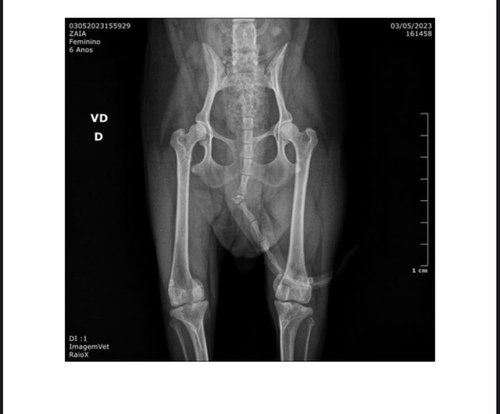

Eu sou a @zayaaugusto. Minha mãe @rosesoaresa criou essa vaquinha porque preciso arrecadar 2,500 reais para fazer duas cirurgias nos meus dois joelhos que deslocaram quando pulei da cama dela.. Agredeço a contribuição de todos! ver tudo

Eu sou a @zayaaugusto. Minha mãe @rosesoaresa criou essa vaquinha porque preciso arrecadar 2,500 reais para fazer duas cirurgias nos meus dois joelhos que deslocaram quando pulei da cama dela.. Agredeço a contribuição de todos!